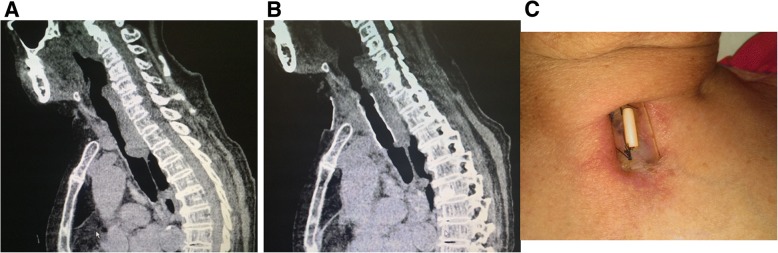

The average follow-up for patients was 5 months (range of 1–13 months). During the follow-up, no stent migration was observed according to CT and bronchoscope (Figs. 2 and 3). The patients’ symptoms disappeared.

Fig. 2.

Preoperative and postoperative images of one patient (Case No. 1). a: Preoperative sagittal CT showing the upper tracheal stenosis. b: Postoperative sagittal CT showing the normal trachea. c: The appearance of the suture fixation on the neck

Fig. 3.

Preoperative and postoperative images of one patient (Case No. 9). a: Sagittal preoperative CT showing the upper tracheal stenosis. b: Postoperative sagittal CT showing the normal trachea. c: The appearance of the suture on the neck